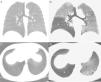

(A) minIP coronal reconstruction of the chest inspiratory CT showing homogeneous pulmonary parenchyma with uniform attenuation. (B) minIP coronal reconstruction of chest expiratory CT, showing a mosaic pattern of the pulmonary parenchyma, with areas of low density (asterisk), alternating with areas of greater attenuation. Low density areas (affecting particularly the right lower lobe and the left lung in a patchy pattern) correspond to areas of air trapping, while the areas of greater density correspond to normal pulmonary parenchyma. (C) minIP axial reconstruction of the chest inspiratory CT showing homogeneous pulmonary parenchyma. (D) minIP axial reconstruction of chest expiratory CT, showing areas of low density (asterisks), related with areas of air trapping.

We report the case of a 44-year-old woman with a history of acute myeloid leukemia, treated 6 months previously with unrelated donor HSCT, who consulted due to dyspnea and dry cough. As a complication of the HSCT, the patient had transitory cytomegalovirus viremia and cutaneous GVHD grade III, which responded favorably to treatment with corticosteroids. No parenchymal opacities were observed on chest radiograph, but chest iCT and eCT revealed a marked mosaic pattern in the pulmonary parenchyma in the expiratory phase, and multiple areas of air trapping were identified in both lungs (Fig. 1), while infectious complications were ruled out. Areas of air trapping on CT can be better viewed with the use of the minimum intensity projection (minIP), an algorithm for visualization of images that enhances areas of less attenuation. Lung function tests (LFT) showed a mild reduction (<20%) in forced expiratory volume in 1 second (FEV1) and increased residual volume (RV) (138%) with respect to pre-HSCT values. No changes were observed on fiberoptic bronchoscopy and bronchoalveolar lavage ruled out opportunistic infections. Given these findings, a diagnosis of BO was given, and the patient responded favorably to treatment with high-dose systemic corticosteroids (stabilization of functional tests).